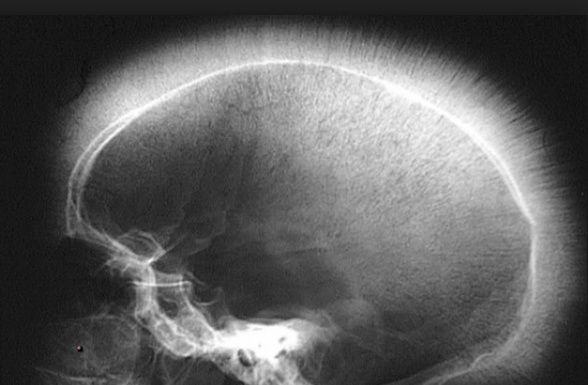

fish bone: Osteomyelitis